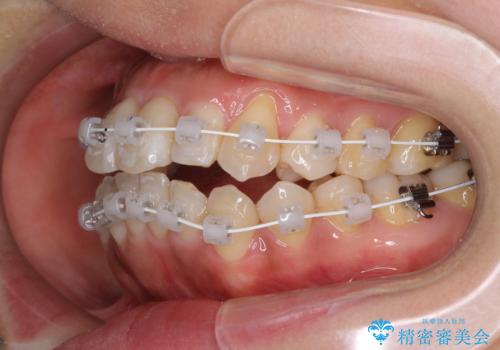

- 審美装置

上顎骨を急速拡大装置により拡大し、ワイヤー装置による抜歯矯正治療を行うこととしました。

治療途中、長期間海外旅行をされたり、帰国後には遠方へ転居されたりと、治療期間が伸びましたが、2年強で治療を終えることができました。